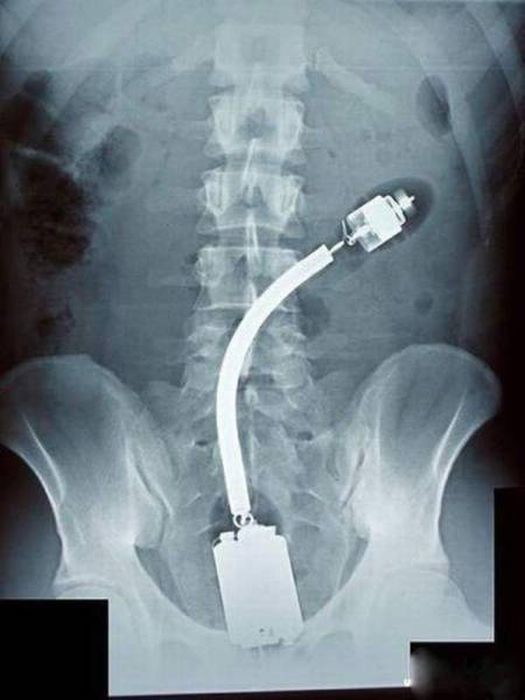

Предметы, которые не очень хочется видеть внутри себя

Под рентгеновскими лучами порой видны не только внутренние органы и кости, но и инородные тела, попавшие в организм

Истории попадания этих предметов в организм могут быть самыми невероятными и запутанными, но больше всего медиков интересует процесс их извлечения, впрочем, в этом заинтересованы и сами пациенты, допустившие нечто подобное со своим телом.